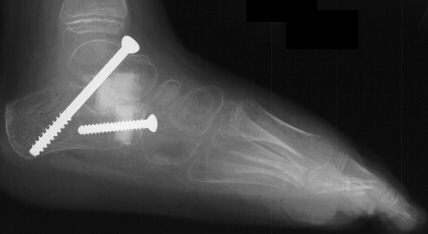

The patient failed conservative management with bracing and therefore

had a bilateral subtalar arthrodesis with lateral column lengthening and

gastrocnemius lengthening

.

Post-operatively, the patient was placed in bilateral short leg casts and

allowed full weight bearing.

At 15 month follow-up the patient had a decrease in her popliteal angles

to 20 degrees and was ambulating with plantigrade feet in neutral varus/valgus

angulation.

Postoperative X-rays:

- Left Talocalcaneal angle is 24 degrees, Talonavicular angle is 2 degrees

- Right Talocalcaneal angle is 28 degrees, Talonavicular angle is 2 degrees